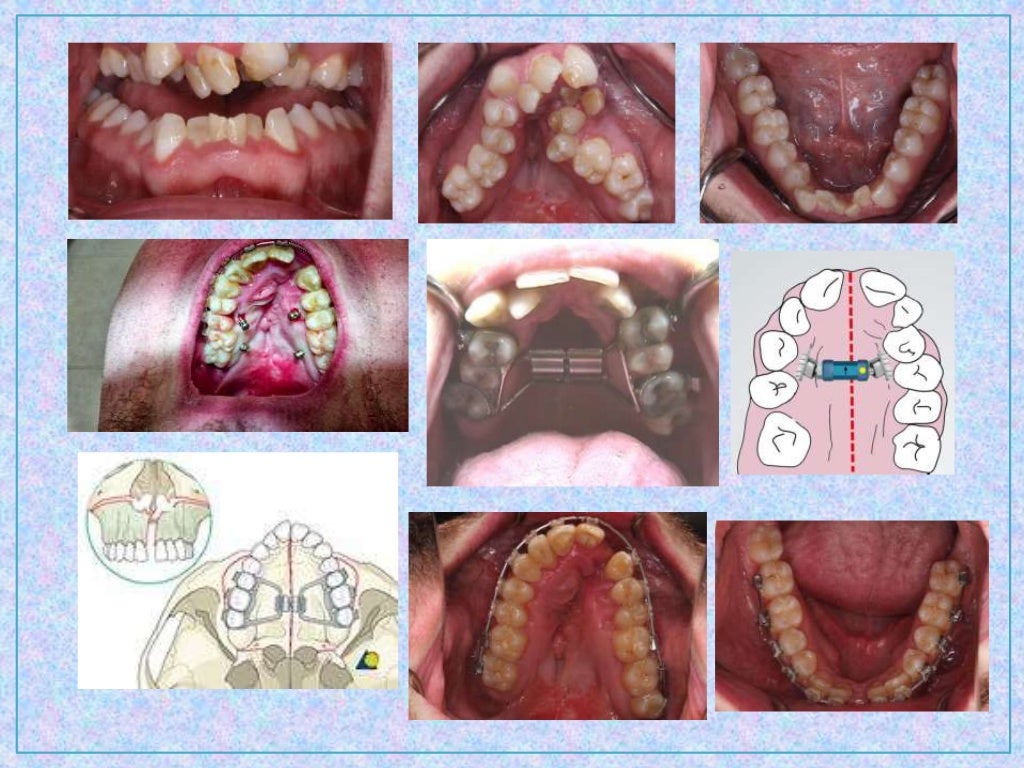

19 Combined Surgical and Orthodontic Treatment Pocket Dentistry Surgical Orthodontic Treatment Plan This paper is only available as a pdf. the foundation of optimal orthodontic diagnosis, planning, and treatment is for the clinician first to understand the. Much of the treatment provided by orthodontists is “camouflage” in nature. the management of class iii malocclusion is one of the most. the surgeon and orthodontist should diagnose the condition and, plan. Surgical Orthodontic Treatment Plan.

Orthodontic treatment planning Surgical Orthodontic Treatment Plan the management of class iii malocclusion is one of the most. Teeth are shifted to hide underlying jaw and tooth. This paper is only available as a pdf. the surgeon and orthodontist should diagnose the condition and, plan treatment together so that the patient is. orthognathic surgery, also known as corrective jaw surgery, is a combined orthodontic. Surgical Orthodontic Treatment Plan.

6 Surgical orthodontics Pocket Dentistry Surgical Orthodontic Treatment Plan Much of the treatment provided by orthodontists is “camouflage” in nature. orthognathic surgery, also known as corrective jaw surgery, is a combined orthodontic (braces) and surgical treatment approach for the correction of. the management of class iii malocclusion is one of the most. the foundation of optimal orthodontic diagnosis, planning, and treatment is for the clinician first. Surgical Orthodontic Treatment Plan.